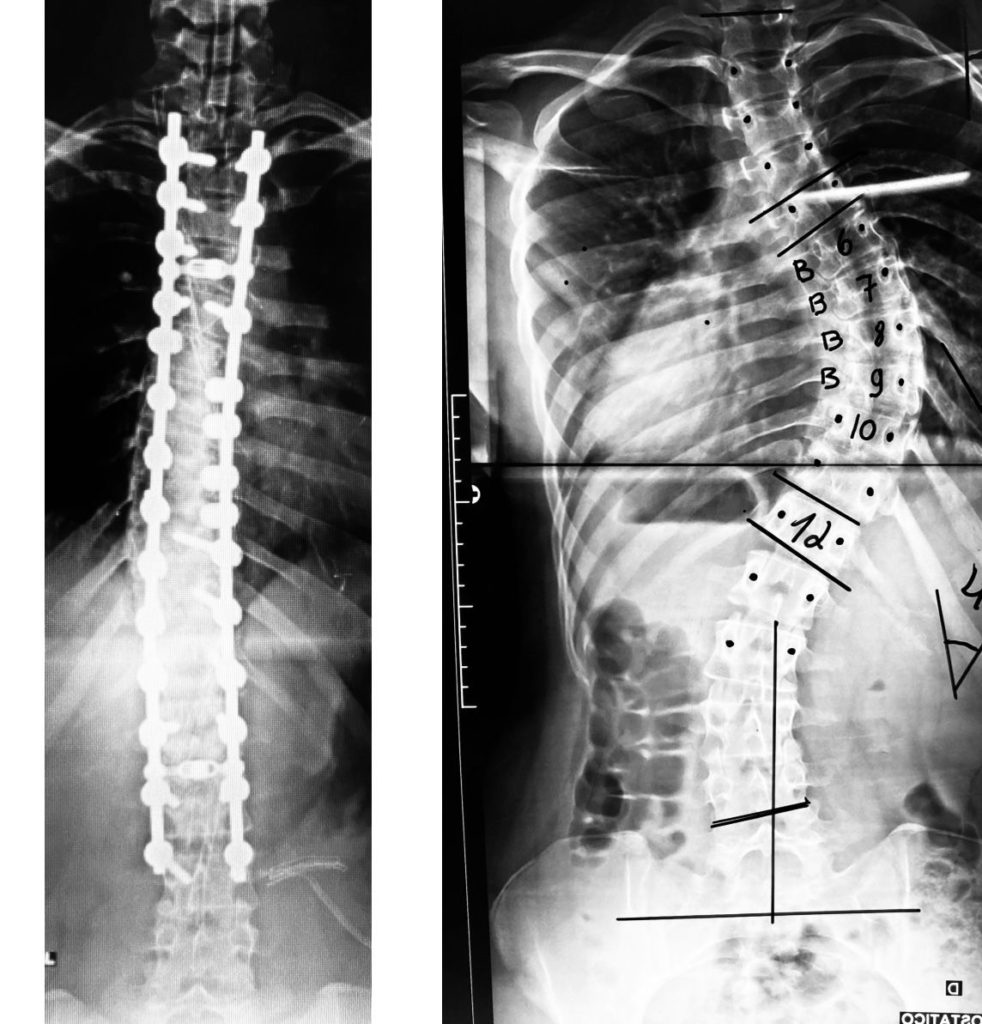

Tratamento Cirúrgico para Escoliose

A escoliose é um desvio da coluna que pode ser de vários tipos e acometer pacientes de todas as faixas etárias e de ambos os …

A escoliose é um desvio da coluna que pode ser de vários tipos e acometer pacientes de todas as faixas etárias e de ambos os